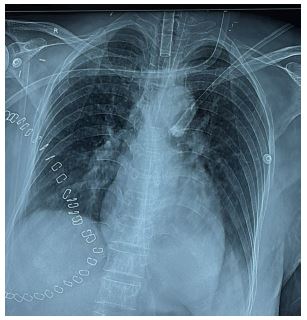

In the postoperative period, the high-sensitivity troponin I level was 779.9 ng/L, well above the normal upper limit of 19 ng/L. Chest X-ray appears normal as shown in (Figure 3).

Figure 3: Chest X-ray of the patient in the postoperative period showing clear lung field.